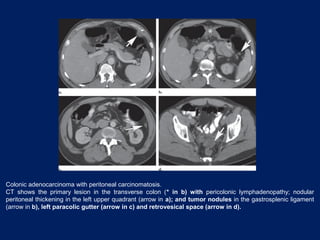

Colonic adenocarcinoma with peritoneal carcinomatosis.

CT shows the primary lesion in the transverse colon (* in b) with pericolonic lymphadenopathy; nodular

peritoneal thickening in the left upper quadrant (arrow in a); and tumor nodules in the gastrosplenic ligament

(arrow in b), left paracolic gutter (arrow in c) and retrovesical space (arrow in d).